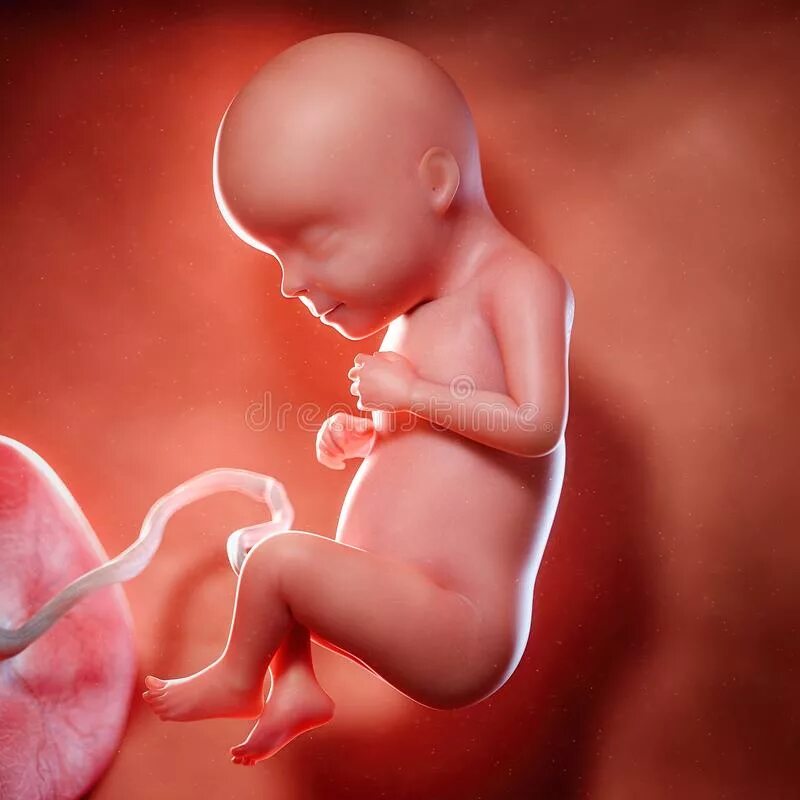

29 недель 4 дня